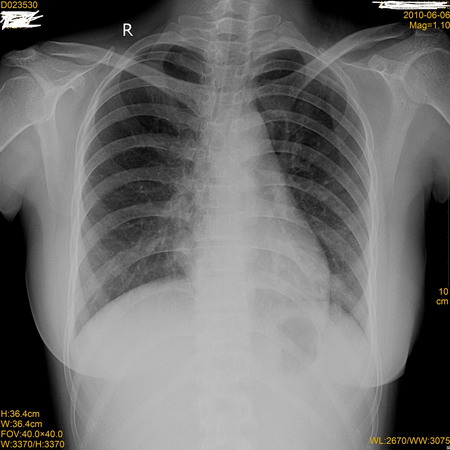

标题: X7496:看看这张胸片!然后再看其CT片!

同行们再看看做的ct片,真的能看到很多,平片也能看到点,你说呢?

右下肺近心缘旁可见-类圆形高密度影,但侧位片上没有看见,建议ct

左下肺炎性改变;没有必要做ct了。右肺无异常。

左下肺炎性改变,请复查。

右侧心缘欠清晰,右下肺炎症?